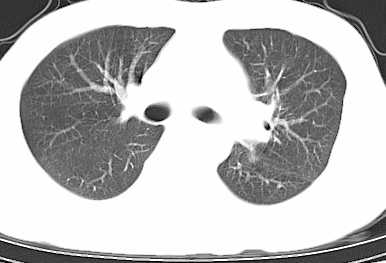

年龄?左侧胸腔中量积液,左下肺见有较多斑片状和大片状影,伴有支气管充气征,考虑:1、左下肺炎;2、结核。肿瘤可以基本排除。

左侧中量胸腔积液伴左肺下叶肺膨胀不全、上肺外围多个小囊样腺泡样病灶。考虑化脓炎症。

1、左侧中量胸腔积液伴左肺下叶肺膨胀不全、。

3 无纵隔肿大淋巴结.

左肺舌叶及下叶见斑片状,大片状高密度影并相应处胸膜及心包不规则增厚,左肺下叶膨胀不全。右肺未见异常,双肺段以上支气管通畅。纵隔左移,其内未见明显肿大淋巴结。左侧胸腔积液。